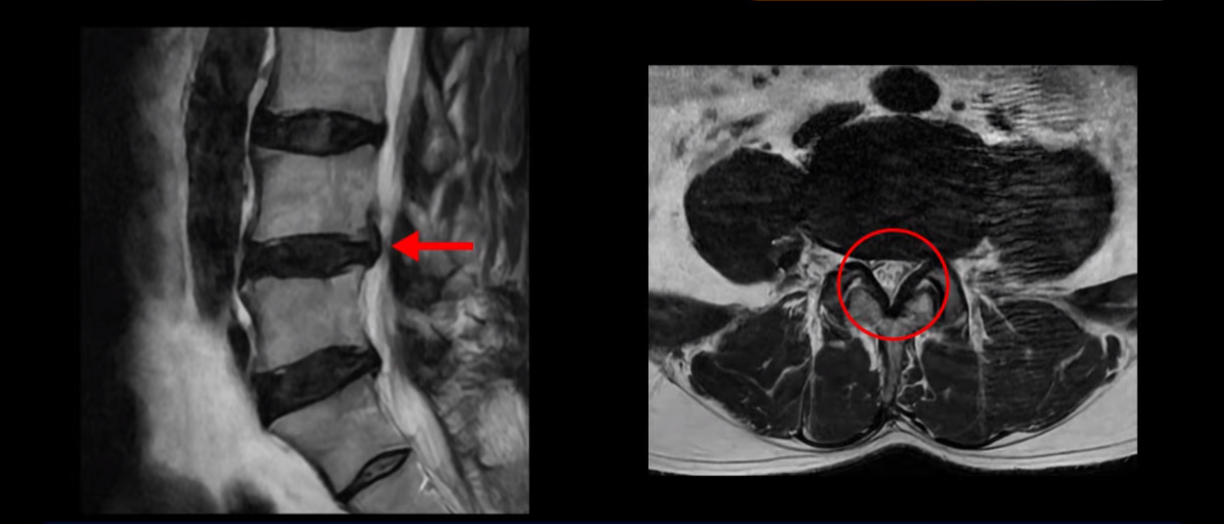

하지만 이분의 갑작스러운 통증을 일으키는 원인은 4번 5번에 발생한 디스크 파열입니다.

20251020_3

원인이 협착이었는지 디스크 파열이었는지 이걸 잘 구별하기 위해서는 환자분의 증상을 자세히 듣고 MRI와 비교해 보셔야 합니다. 증상을 자세히 듣지 않고 MRI만 쳐다보고 진료하면 디스크인지 협착증인지 오진할 수 있습니다.

이분은 왼쪽 무릎 아래로 본인 표현으로는 다리를 잘라 버리고 싶다고 할 정도의 심한 통증이 있는데 보통 이런 표현은 디스크 파열이 발생했을 때 많이 사용하는 표현입니다. 이분 4번 5번 디스크를 자세히 보면 왼쪽으로 파열되어 밀려 올라간 디스크 수핵을 볼 수 있습니다.